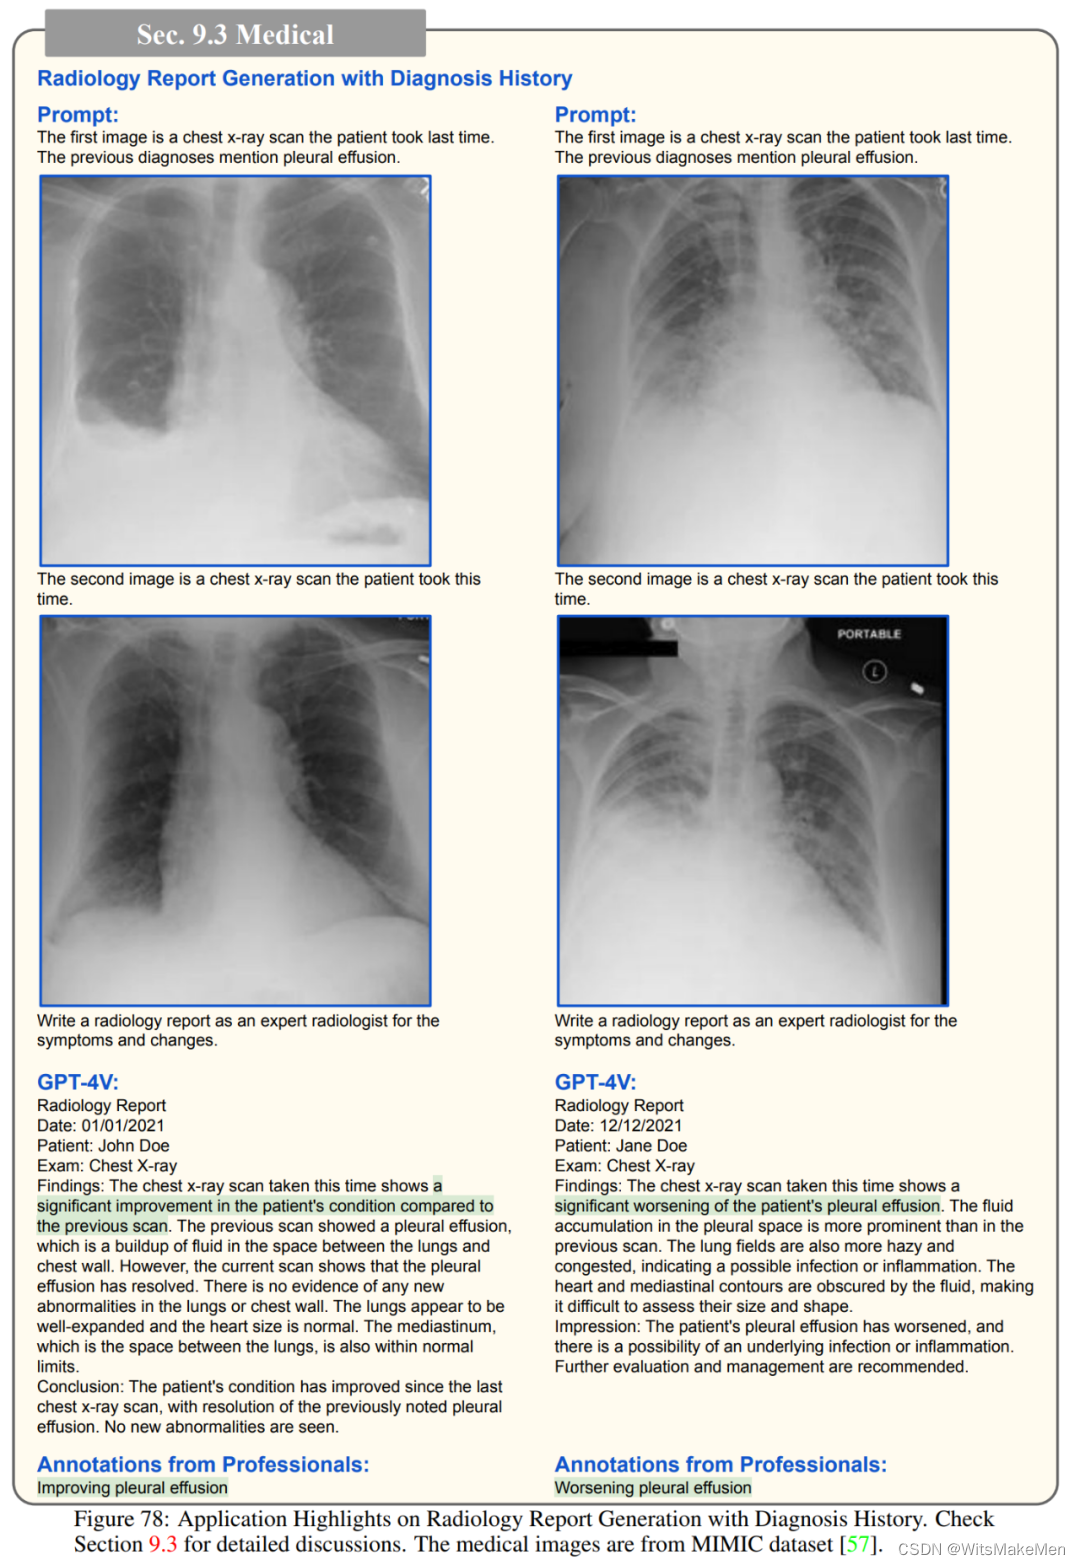

除此以外,GPT-4V还可以识别常见的疾病,例如其能根据肺部的CT扫描指出潜在的问题,又或者对给定的x光片中的牙齿和颌骨,解释下颌左下方和右侧部分出现的智齿可能需要切除;GPT-4V能正确识别徽标,并提供详细的描述,包括其设计,颜色,形状和符号;如果提示中出现的问题与照片不符,GPT-4V也能进行反事实推理。

医药